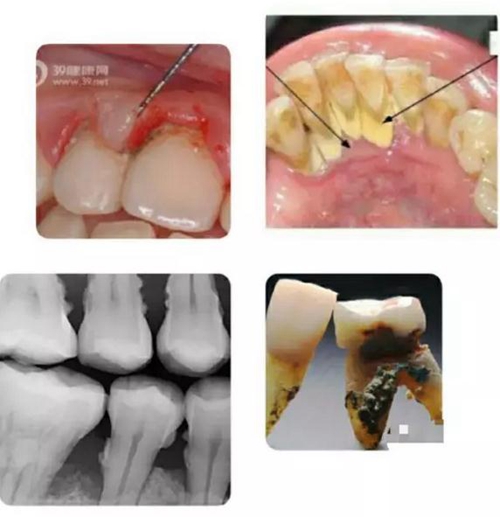

如上圖所示,無論是肉眼直視,還是在X光片上顯現(xiàn),以及拔下的牙齒之上,牙周病患者的牙根面上都可見附著著大大小小的牙結石。

寄居在牙結石里的細菌可以釋放大量毒素,導致牙齦發(fā)炎,溶解,與牙面分離,從而突破牙槽骨保護的第一道屏障;繼而進一步直接使牙槽骨發(fā)炎,溶解,萎縮。若無牙科治療介入,牙槽骨可以被溶解殆盡,最終牙齒自行脫落。一般來講,牙齒上的牙結石越大越多,寄居的細菌就越多,牙周病就發(fā)展得越迅速越嚴重。

上列組圖大致列出了牙結石的成因: 首先是牙齒的復雜形狀與排列,形成有很多死角空間 ;其次是我們吃的食物會進入到這些死角空間里,而目前人們的刷牙工具和方法與各人刷牙的效果并不能保證所有食物殘渣被完全清除干凈。于是混合著口腔中天然存在的細菌,在舌肌頰肌唇肌等口腔周圍肌肉的擠壓下,殘留食物便緊粘在牙面上,并沉積了唾液中所含的鈣質后,便形成了堅硬的牙結石,靠自己刷牙不可去掉。必須由經(jīng)過專業(yè)訓練的牙醫(yī)或潔牙員使用專門工具才能清除。